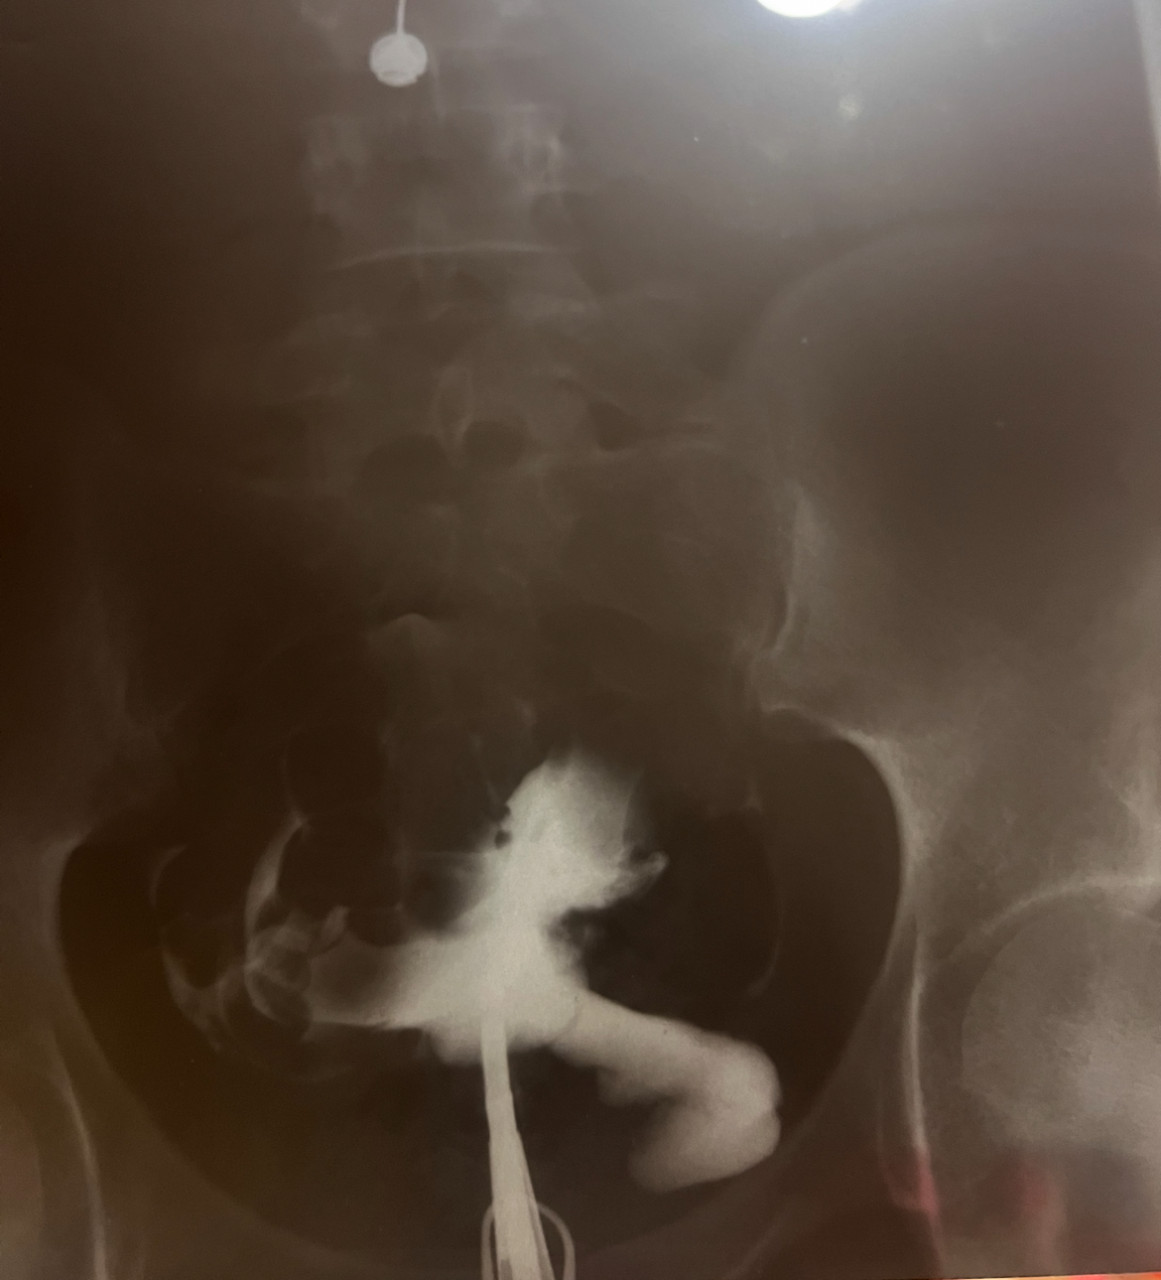

Здравствуйте. Помогите пожалуйста расшифровать снимок ГСГ маточных труб. Можно ли по нему сказать о проходимости или не проходимости маточных труб?

Здравствуйте. По представленным рентгеновским снимкам ГСГ контраст заполняет полость матки и проксимальные отделы маточных труб, но выхода контраста в брюшную полость, который указывает на проходимость труб, не видно. Это может говорить о неполной или полной непроходимости, однако для точного заключения нужно описание врача-рентгенолога проводившего исследование, так как оценка зависит от всех фаз исследования и качества снимков (вы предоставили фото снимков и может быть искажение).